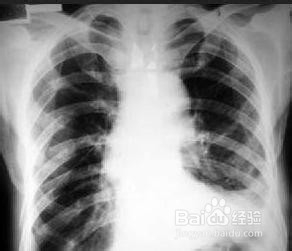

2、2.胸部骨折:一处肋骨骨折 30日~40日;多根;多处肋骨骨折 90日;胸骨骨折 90日。